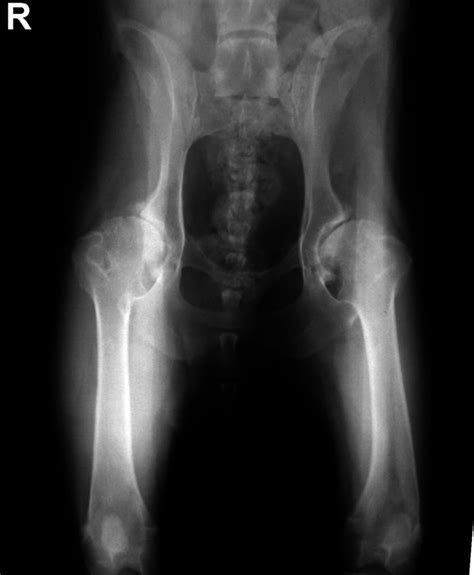

Ochorenie sa dá zdiagnostikovať a určiť stupeň dysplázie jedine RTG vyšetrením vykonanom v celkovej anestézii na oficiálne schválenom RTG pracovisku. Od 12 týždňov veku je možné vykonať tzv. rannú diagnostiku DBK. V prípade podozrenia na dysplaziu sa diagnostika vykonáva ihneď bez ohľadu na vek. Pre účely chovnosti je jedinec vyšetrovaný po dosiahnutí určitého veku (v závislosti od plemena od 12,18, či 24 mesiacov ).

Diagnostika DKK je podľa noriem Medzinárodnej Kynologické Federácie (FCI) vykonávaná rentgenologicky. Podľa tejto metódy sa diagnostikuje DKK vo všetkých krajinách, ktoré sú členmi FCI (väčšina európskych krajín, Rusko, Južná Amerika a Ázia). V USA a Kanade je používaná odlišná norma - OFA (Orthopedic Foundation for Animals) a vo Veľkej Británii, Írsku, Novom Zélande a v Austrálii je používaná norma BVA / KC (British Veterinary Association / Kennel Club). Podľa noriem FCI je röntgenologické vyšetrenie vykonávané vo veku 12-18 mesiacov. Pri jednotlivých plemien psov je určený vek, v ktorom je vyšetrenie vykonávané, záväznými podmienkami príslušného chovateľského klubu.

Pri vyšetrení sa sleduje laxicita kĺbov a následne pri röntgenologickom vyšetrení sa meria miera pohyblivosti kĺbovej hlavice ku kĺbovej jamke. Dysplázia bedrového kĺbu sa medzinárodne označuje ako HD (hip dysplasia). Vyhodnocuje sa ľavý i pravý kĺb, zápisy HD 0/0 alebo HD A/A predstavujú zdravé kĺby bez nálezu. Čím vyššie číslo (resp. písmeno), tým vyšší stupeň dysplázie.

V prípade, že sú už príznaky ochorenia rozvinuté, tak bolestivosť je neúnosná. Na potvrdenie, lokalizáciu a určenie miery rozvoja DBK sa vykonáva minimálne RTG vyšetrenie a v niektorých prípadoch sa odporúča CT.